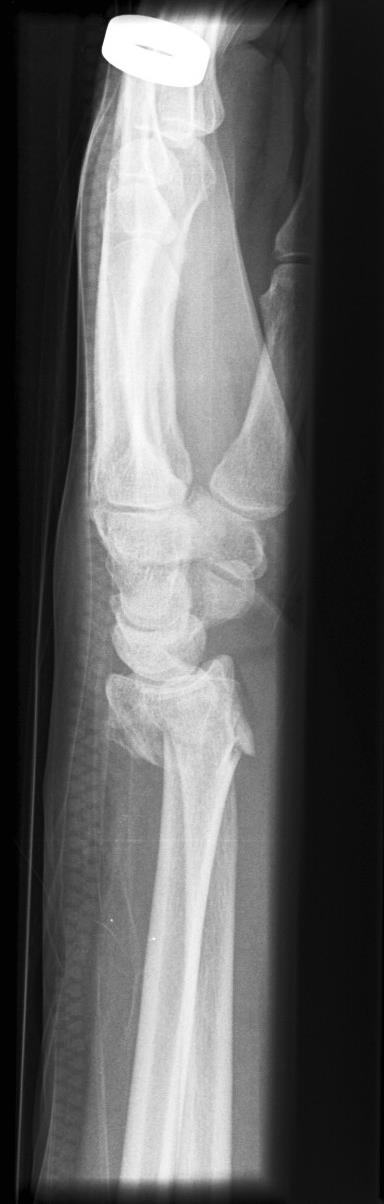

• Dorsal Barton

• Fracture-dislocation of radiocarpal joint with intra-articular fx involving the dorsal lip